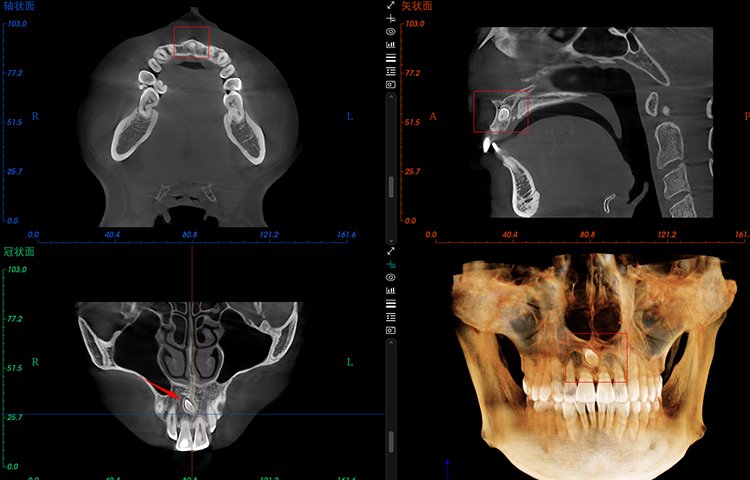

El software de diagnóstico 3D líder de Meyer y el sistema de análisis ortodóntico inteligente adoptan un diseño de UI modular, lo que hace que las funciones del software sean más cercanas a las necesidades clínicas y más fáciles de usar para los médicos, reduciendo significativamente el costo de aprendizaje.

Software de Diagnóstico 3D

MyDentViewer